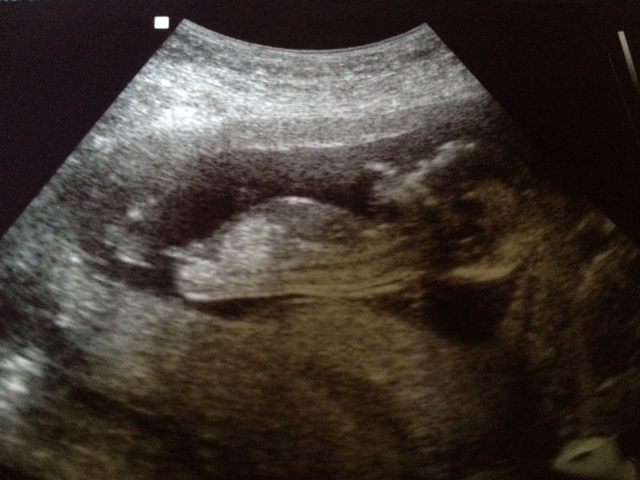

and a cute profile just cause I love her :D

Attachment 2766